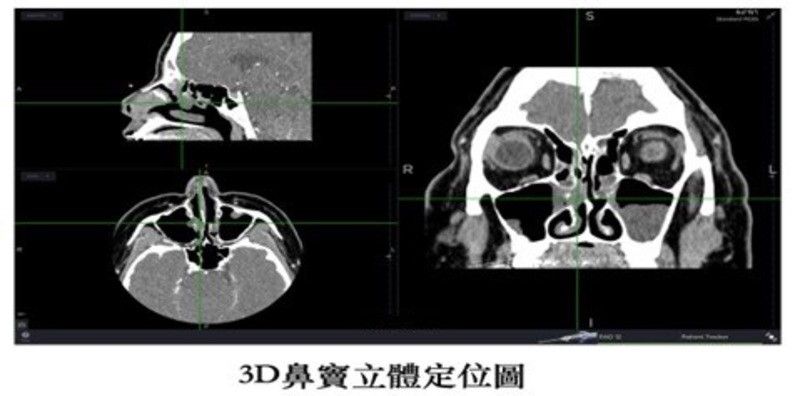

高解析3D導航定位系統 增加手術安全性、精準移除病灶

根據世界大型文獻統計,鼻竇炎手術一年內復發率為3.5%,5年內復發率為6.5%。人類的鼻竇極其複雜,過去醫師難以確定是否有將病灶完全清除乾淨。3D導航定位系統,利用光學或磁力定位,繪製出個人化的鼻竇圖形,清楚顯示病灶與正常鼻竇組織。原理是將電腦斷層影像上傳至導航系統,建立個人即時3D立體鼻竇影像,誤差範圍只有1~2mm。讓醫師在手術時精準移除病灶,確保眼睛跟顱部等中樞神經組織的安全性,提升治癒率。另外,過去在處理較為深處的鼻竇如後篩竇、蝶竇及顱底部分,手術視野較為昏暗。高解析4K螢幕系統,相較於傳統HD系統,提升畫素、對比度及明亮度,對於神經與血管等重要組織,能夠看得更清楚,增加手術安全性。文獻顯示,病患術後在10年追縱下,生活品質獲得相當大的改善,顯示鼻竇手術治療的高成功率及術後效果。3D立體定位導航系統目前已納入健保給付範圍,患者不需要額外自費。